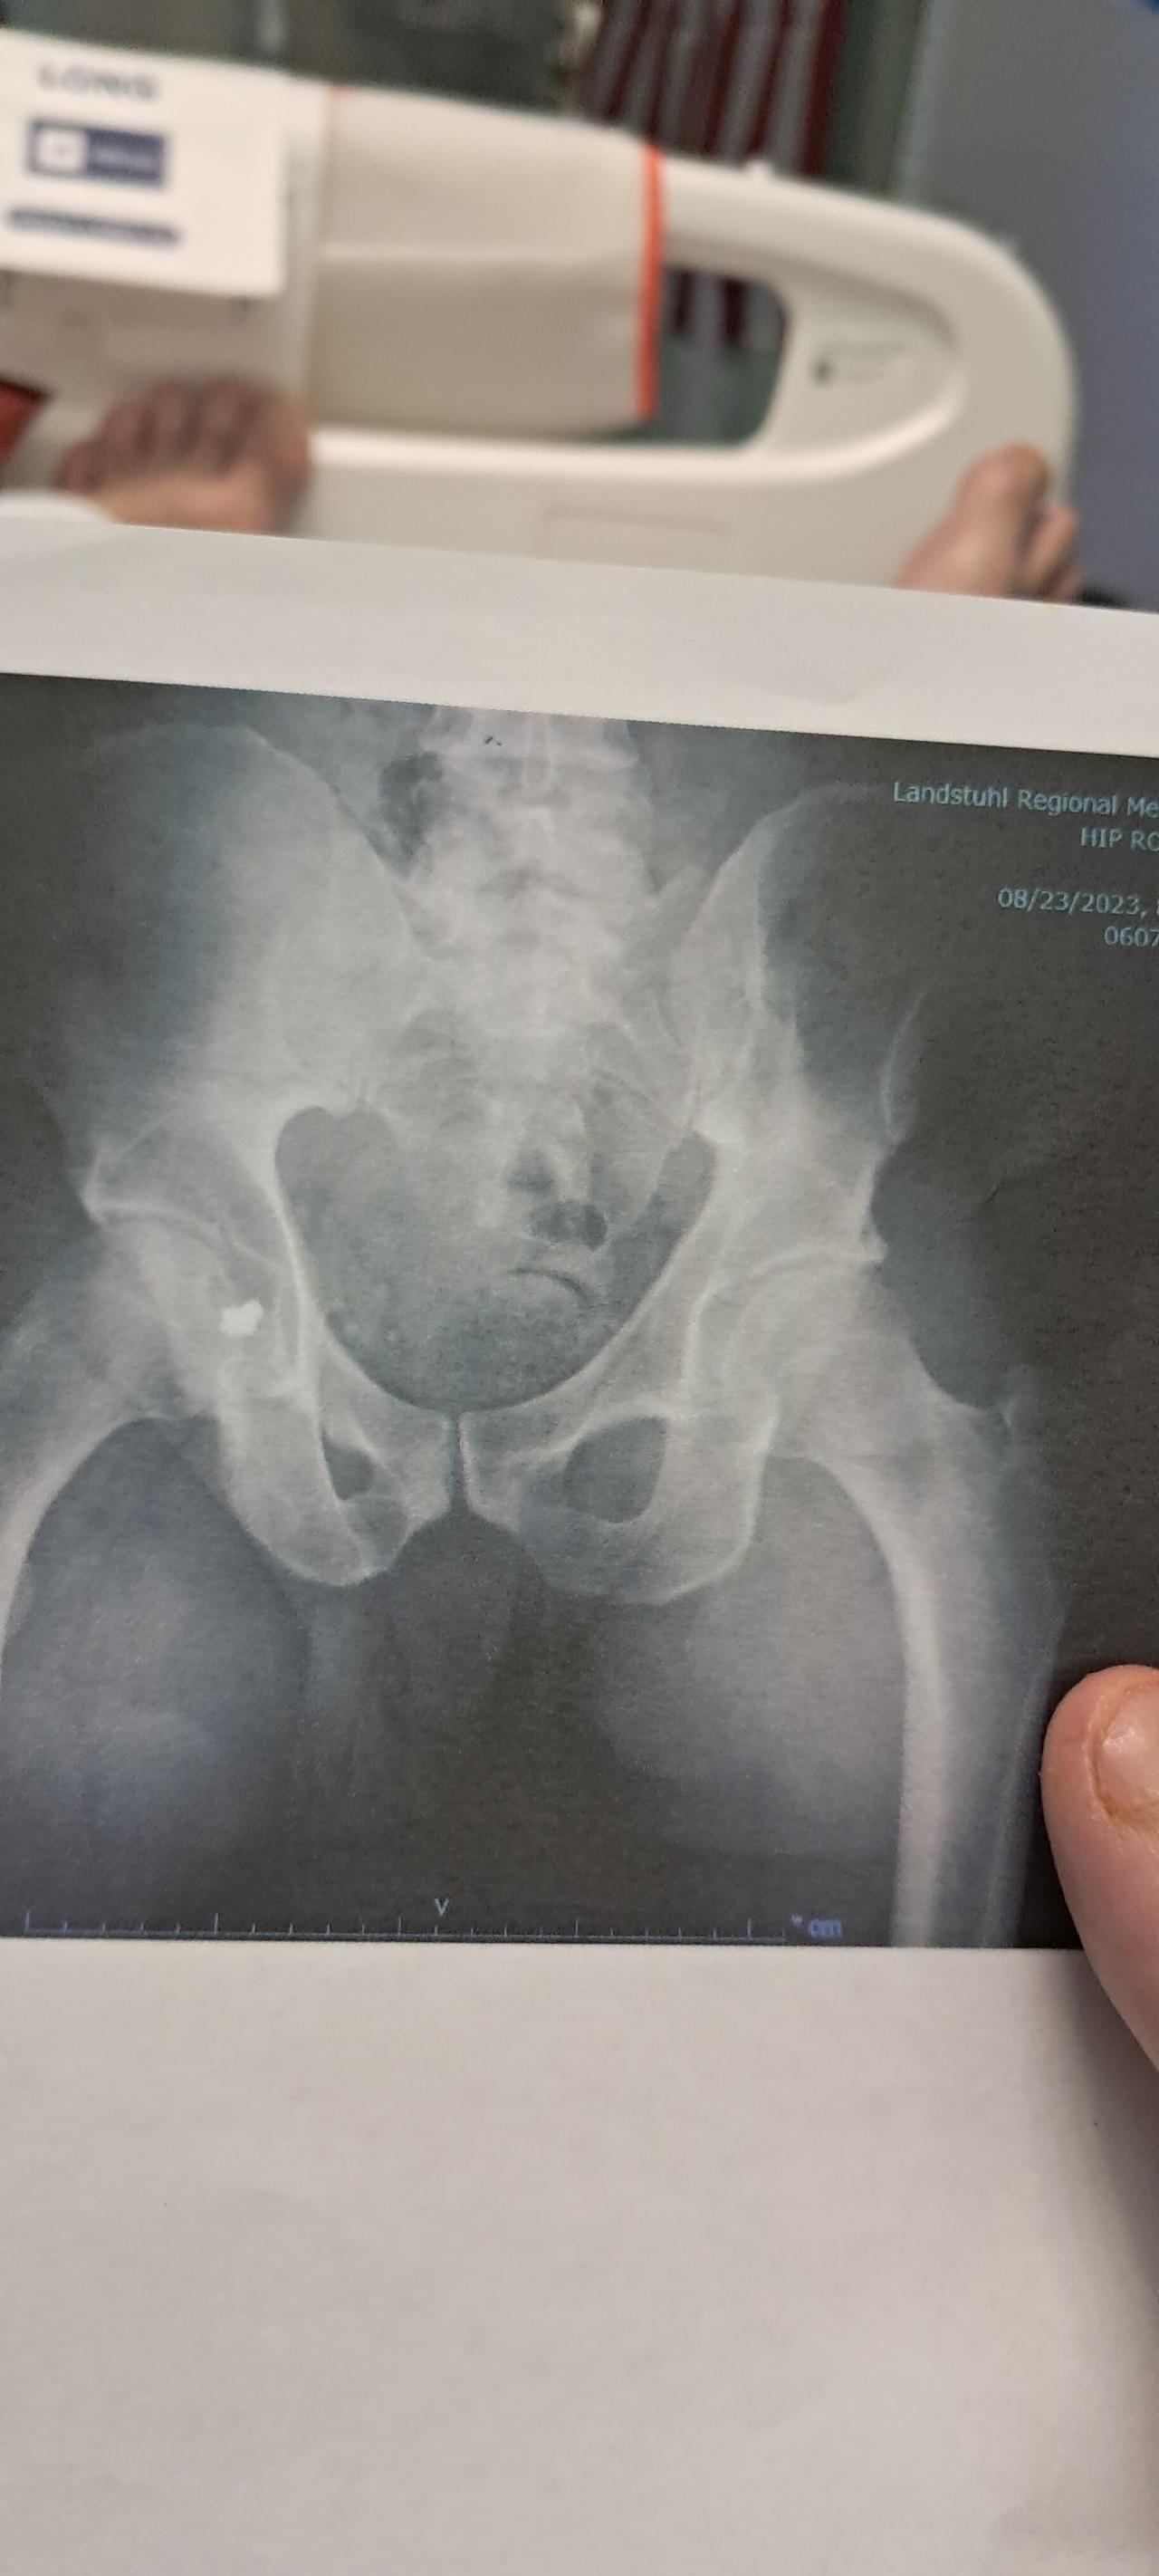

Main image

So turns out shrapnel in my hip cutting into the sciatic nerve is the main cause of problems I'm my leg ...hopefully once that's out healing can start